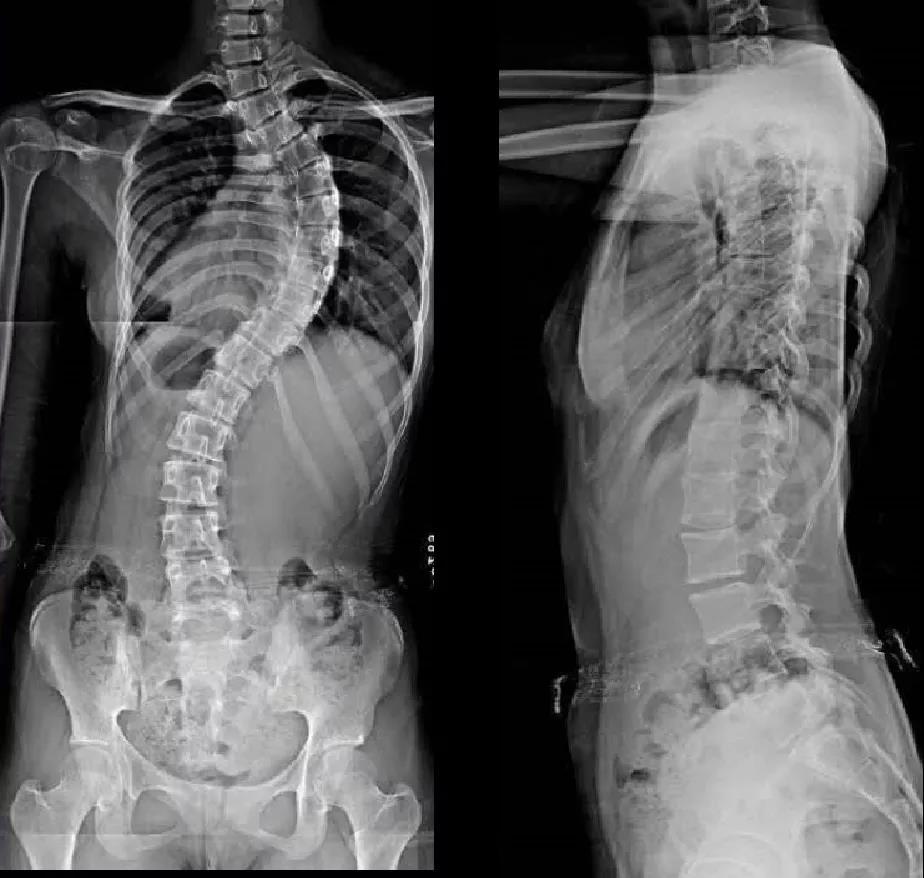

脊柱侧弯是脊柱的三维畸形,冠状面侧方弯曲,水平面轴向旋转,矢状面生理弯曲,前凸或后凸异常。而超过80%的脊柱侧弯是原因不明的,好发于青少年特发性脊柱侧弯,其中又以女性最为多见。

(脊柱矢状面上胸椎后凸,冠状面上S型弯曲,腰椎前凸曲度减少,椎体和骨盆旋转)QUESTION-02

QUESTION-03脊柱侧弯如何检查?

第三步:拍影像学阶段

目前国际上公认的方法就是手术治疗和保守治疗,通常根据患者的年龄、性别、剩余生长潜力、躯干旋转角度及Cobb角(脊柱侧弯严重程度的参考标准之一)的大小等因素来选择合适的治疗方案。